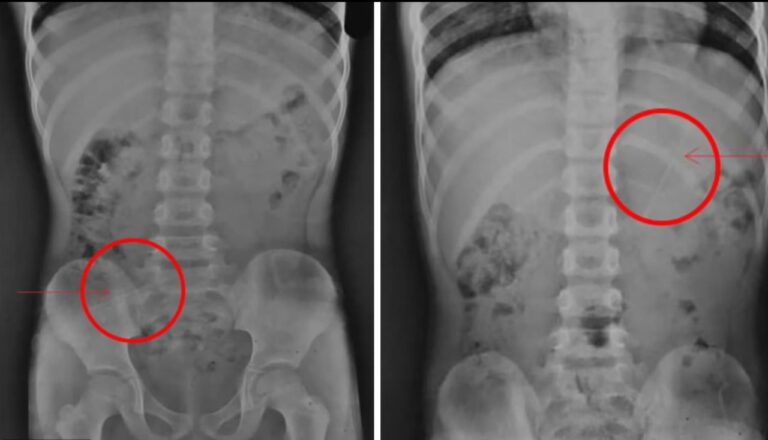

Um menino, 7, sobreviveu após engolir acidentalmente um lápis de 10 centímetros. O caso aconteceu no Nepal. No hospital, os médicos fizeram radiografias no menino.

Não há informações de como o menino engoliu o lápis. A criança não precisou passar por cirurgia e ficou sem ferimentos. A imagem do tórax do menino mostrou que o lápis estava no estômago dele. De acordo com as informações, o menino ficou em observação, podendo comer apenas banana e beber bastante líquido.